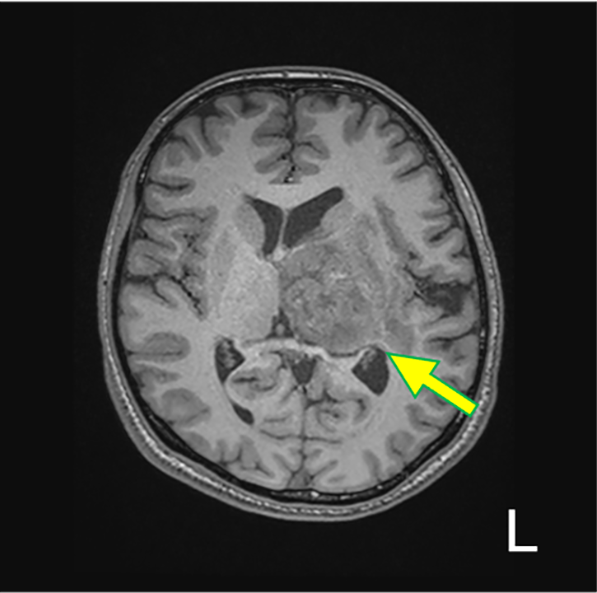

症例・導⼊事例 パンくず ホーム 症例紹介・導入事例 症例紹介 イオプロミド注「BYL」 製品・部位から探す 全て イオプロミド注「BYL」ガドビスト®静注1.0mol/Lその他の造影剤心臓・大血管肺・縦隔乳房腹部・骨盤消化管泌尿器男性生殖器女性生殖器四肢脳・脊髄頭頸部 イオプロミド注「BYL」症例一覧 胸骨圧迫に伴う動脈損傷の一例 胸骨圧迫に伴う動脈損傷の一例 胸骨圧迫に伴う動脈損傷の一例 2025-12-23 東京医科大学病院Aquilion64キャノンメディカルシステムズ株式会社2025 詳細はこちら 腎血管筋脂肪腫のIVR術前CT 腎血管筋脂肪腫のIVR術前CT 腎血管筋脂肪腫のIVR術前CT 2025-12-23 東京医科大学病院Revolution FrontierGE Healthcare2025 詳細はこちら 急性大動脈解離の造影CT 急性大動脈解離の造影CT 急性大動脈解離の造影CT 2026-01-08 東京医科大学病院Aquilion Prime SPキャノンメディカルシステムズ株式会社2025 詳細はこちら 肺血栓塞栓症および深部静脈血栓症の診断 肺血栓塞栓症および深部静脈血栓症の診断 肺血栓塞栓症および深部静脈血栓症の診断 2025-12-23 東京医科大学病院Revolution CTGE Healthcare2025 詳細はこちら 外傷性内頸動脈解離による閉塞が原因と考えられる脳梗塞の1例 外傷性内頸動脈解離による閉塞が原因と考えられる脳梗塞の1例 外傷性内頸動脈解離による閉塞が原因と考えられる脳梗塞の1例 2025-12-17 奈良県立医科大学附属病院Aquilion ONEキャノンメディカルシステムズ株式会社2025 詳細はこちら 頭部CTでのSAH術後血流評価 頭部CTでのSAH術後血流評価 頭部CTでのSAH術後血流評価 2025-12-17 奈良県立医科大学附属病院Aquilion ONEキャノンメディカルシステムズ株式会社2025 詳細はこちら 島回部膠芽腫の1例 島回部膠芽腫の1例 島回部膠芽腫の1例 2025-12-17 奈良県立医科大学附属病院Aquilion ONEキャノンメディカルシステムズ株式会社2025 詳細はこちら 直腸静脈瘤に対する経皮経肝的静脈瘤塞栓術 直腸静脈瘤に対する経皮経肝的静脈瘤塞栓術 直腸静脈瘤に対する経皮経肝的静脈瘤塞栓術 2025-12-24 日本医科大学武蔵小杉病院Revolution HDGE Healthcare2025 詳細はこちら 膵尾部癌のステージング目的の造影CT 膵尾部癌のステージング目的の造影CT 膵尾部癌のステージング目的の造影CT 2025-12-17 奈良県立医科大学附属病院Aquilion ONEキャノンメディカルシステムズ株式会社2025 詳細はこちら 胸部急性大動脈解離に対する全弓部置換術後の活動性出血 胸部急性大動脈解離に対する全弓部置換術後の活動性出血 胸部急性大動脈解離に対する全弓部置換術後の活動性出血 2025-12-17 杏林大学医学部付属病院Aquilion ONE ViSION Editionキャノンメディカルシステムズ株式会社2025 詳細はこちら 症例紹介・導入事例一覧ページへ戻る